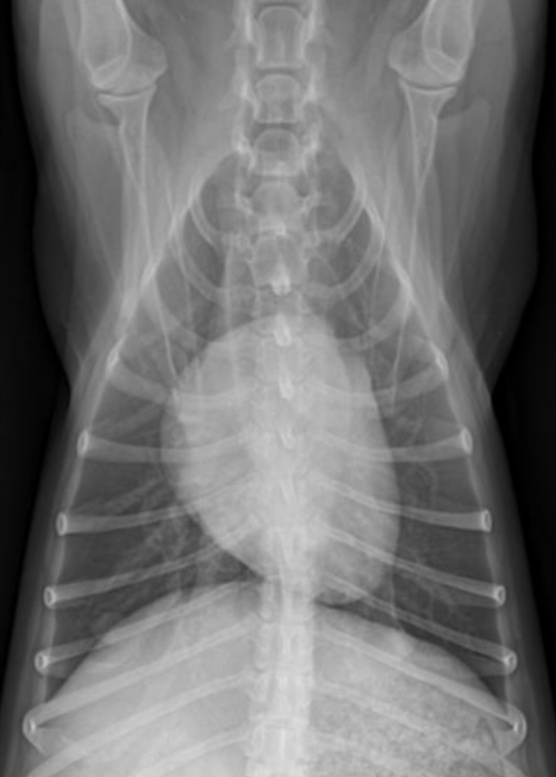

| DV (Dorso-ventral) | VD (Ventro-dorsal) |

|---|---|

![]() | ![]() |

| 심장 관찰에 좋음. | 폐 관찰에 좋음. |

| 기흉 있을 때 좋음. (pleural air) | 흉수 있을 때 좋음. (pleural fluid) (바르게 놓인 삼각형 모양 - 흉수가 아래-옆으로 퍼짐) |

| 응급 환자에서 필요. (원래 자세 그대로) |